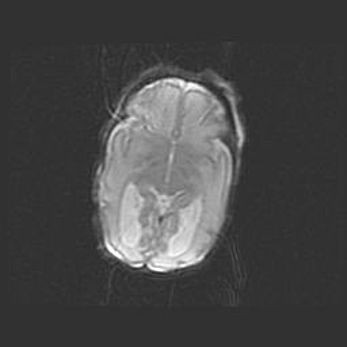

Множественные кисты обоих полушарий головного мозга, наибольшая из них в правой затылочной области. Ассиметричная атрофическая гидроцефалия.

Возраст: 7 месяцев

Вес: 5660 г

Пол: мужской

Окружность головы: 41,5 см

Срок гестации: 28-29 недель

Кисты головного мозга развиваются в результате многоочаговых некрозов вещества мозга и возникают вследствие перенесенной перинатальной инфекции, менингитов, энцефалитов, асфиксии, родовой травмы, расстройств мозгового кровообращения различного генеза. Образованию кист в веществе головного мозга плодов и новорожденных способствуют такие факторы, как высокое содержание в нем воды, недостаточная (или отсутствие) миелинизация и слабая астроглиальная реакция на повреждение.

Кисты могут сочетаться с гидроцефалией и другими поражениями головного мозга.